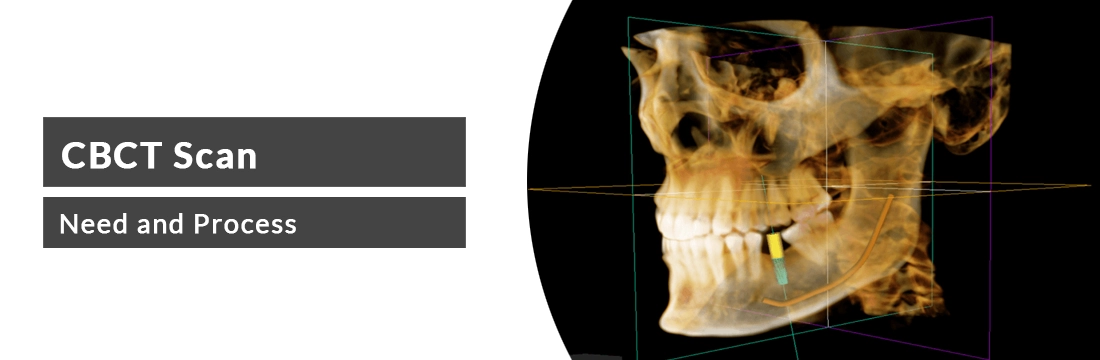

This article will elaborate on the CBCT scan, Its need and its process.

What is a CBCT scan?

CBCT is the short form of cone beam computed tomography. CBCT is the imaging tool that uses the X-rays to evaluate the conditions related to dentistry. This is used to evaluate the bone structures, nerve pathways and surrounding tissues of the teeth.